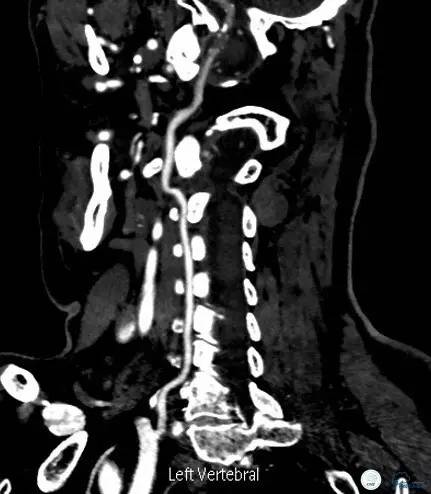

头颈部CTA(图3-6):双侧椎动脉远端及基底动脉近端混合斑块、管腔中-重度狭窄,双侧大脑后动脉纤细。

图3